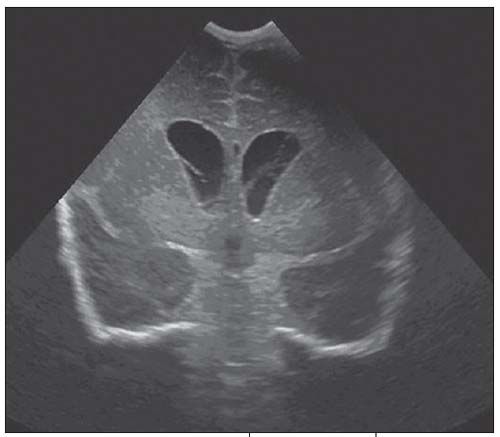

Figure 1 – Coronal cranial ultrasonogram shows hydrocephalus. Echogenic ependymal lining of the lateral ventricles represents ventriculitis. Linear echogenic strands within the ventricles are consistent with synechiae.

On day 2 of hospitalization, a cranial ultrasonogram revealed hydrocephalus, with echogenic ependyma of the lateral ventricles, related to ventriculitis (Figure 1). Linear synechiae noted within the ventricles were characteristic of inflammation. The 3rd and 4th ventricles were normal. The findings represented a noncommunicating hydrocephalus at the level of the Monro foramen. A week later, a follow-up ultrasonogram showed resolution of the hydrocephalus and reabsorption of the intraventricular echogenic strands (Figure 2); there was no evidence of a focal brain lesion. A contrast-enhanced CT scan on day 17 revealed enhancement of the ependymal lining of the lateral ventricles with no hydrocephalus (Figure 3). Slight cisternal enlargement at the left lateral cerebral convexity and right frontal region, consistent with sympathetic effusion (exudative effusion caused by disease in nearby structure), was also present. The parenchyma was normal.